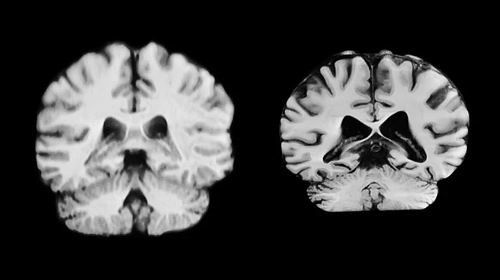

健康大脑(左)和患有阿尔茨海默病的大脑。图片来源:Anatomical Travelogue/SPL

一项10月13日发表于美国《国家科学院院刊》的研究表明,在衰老过程中,男性大脑更多区域减少的体积比女性更大。研究者认为,这意味着与年龄相关的大脑变化并不能解释为何女性更容易被诊断出患有阿尔茨海默病。

临床上被诊断患有阿尔茨海默病的女性几乎是男性的两倍,而衰老是该疾病的最大风险因素。这促使研究者开始探索大脑中与年龄相关的性别差异。“如果女性大脑衰退程度更严重,或许有助于解释为何她们患阿尔茨海默病的可能性更大。”论文第一兼通讯作者、挪威奥斯陆大学的Anne Ravndal表示。